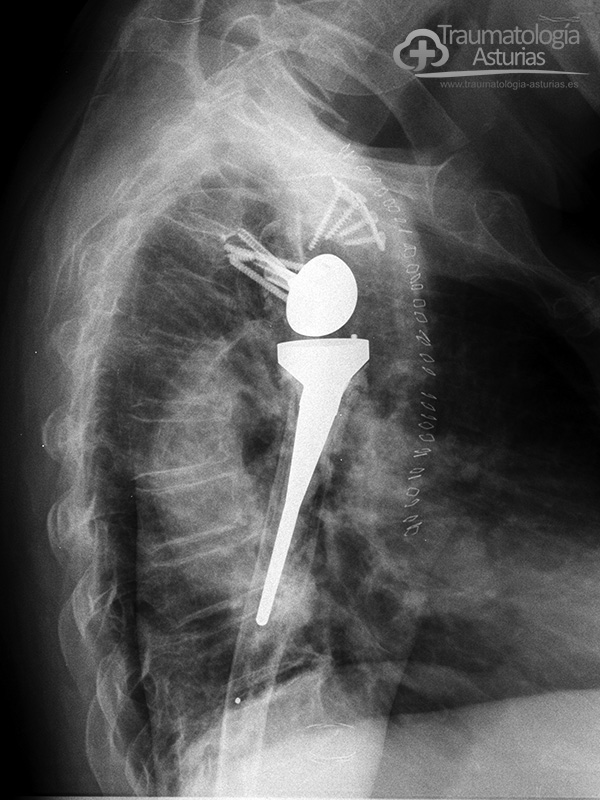

Las cirugías protésicas repetidas en el hombro procovan un déficit del tejido óseo, sobre todo glenoideo, que requiere el uso de injertos óseos y el uso de técnicas quirúrgicas originales para dar estabilidad primaria a la articulación como en este caso un tornillo guia canulado a la fosa supraespinosa y el tope óseo acromio-coracoideo apoyado en placa de osteosíntesis